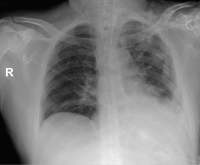

Thoraxröntgen

Abbildung 2: Thoraxröntgen 27.02.2022

Keywords:

Pneumologie

,

Pulmonalvenenstenose

PVS